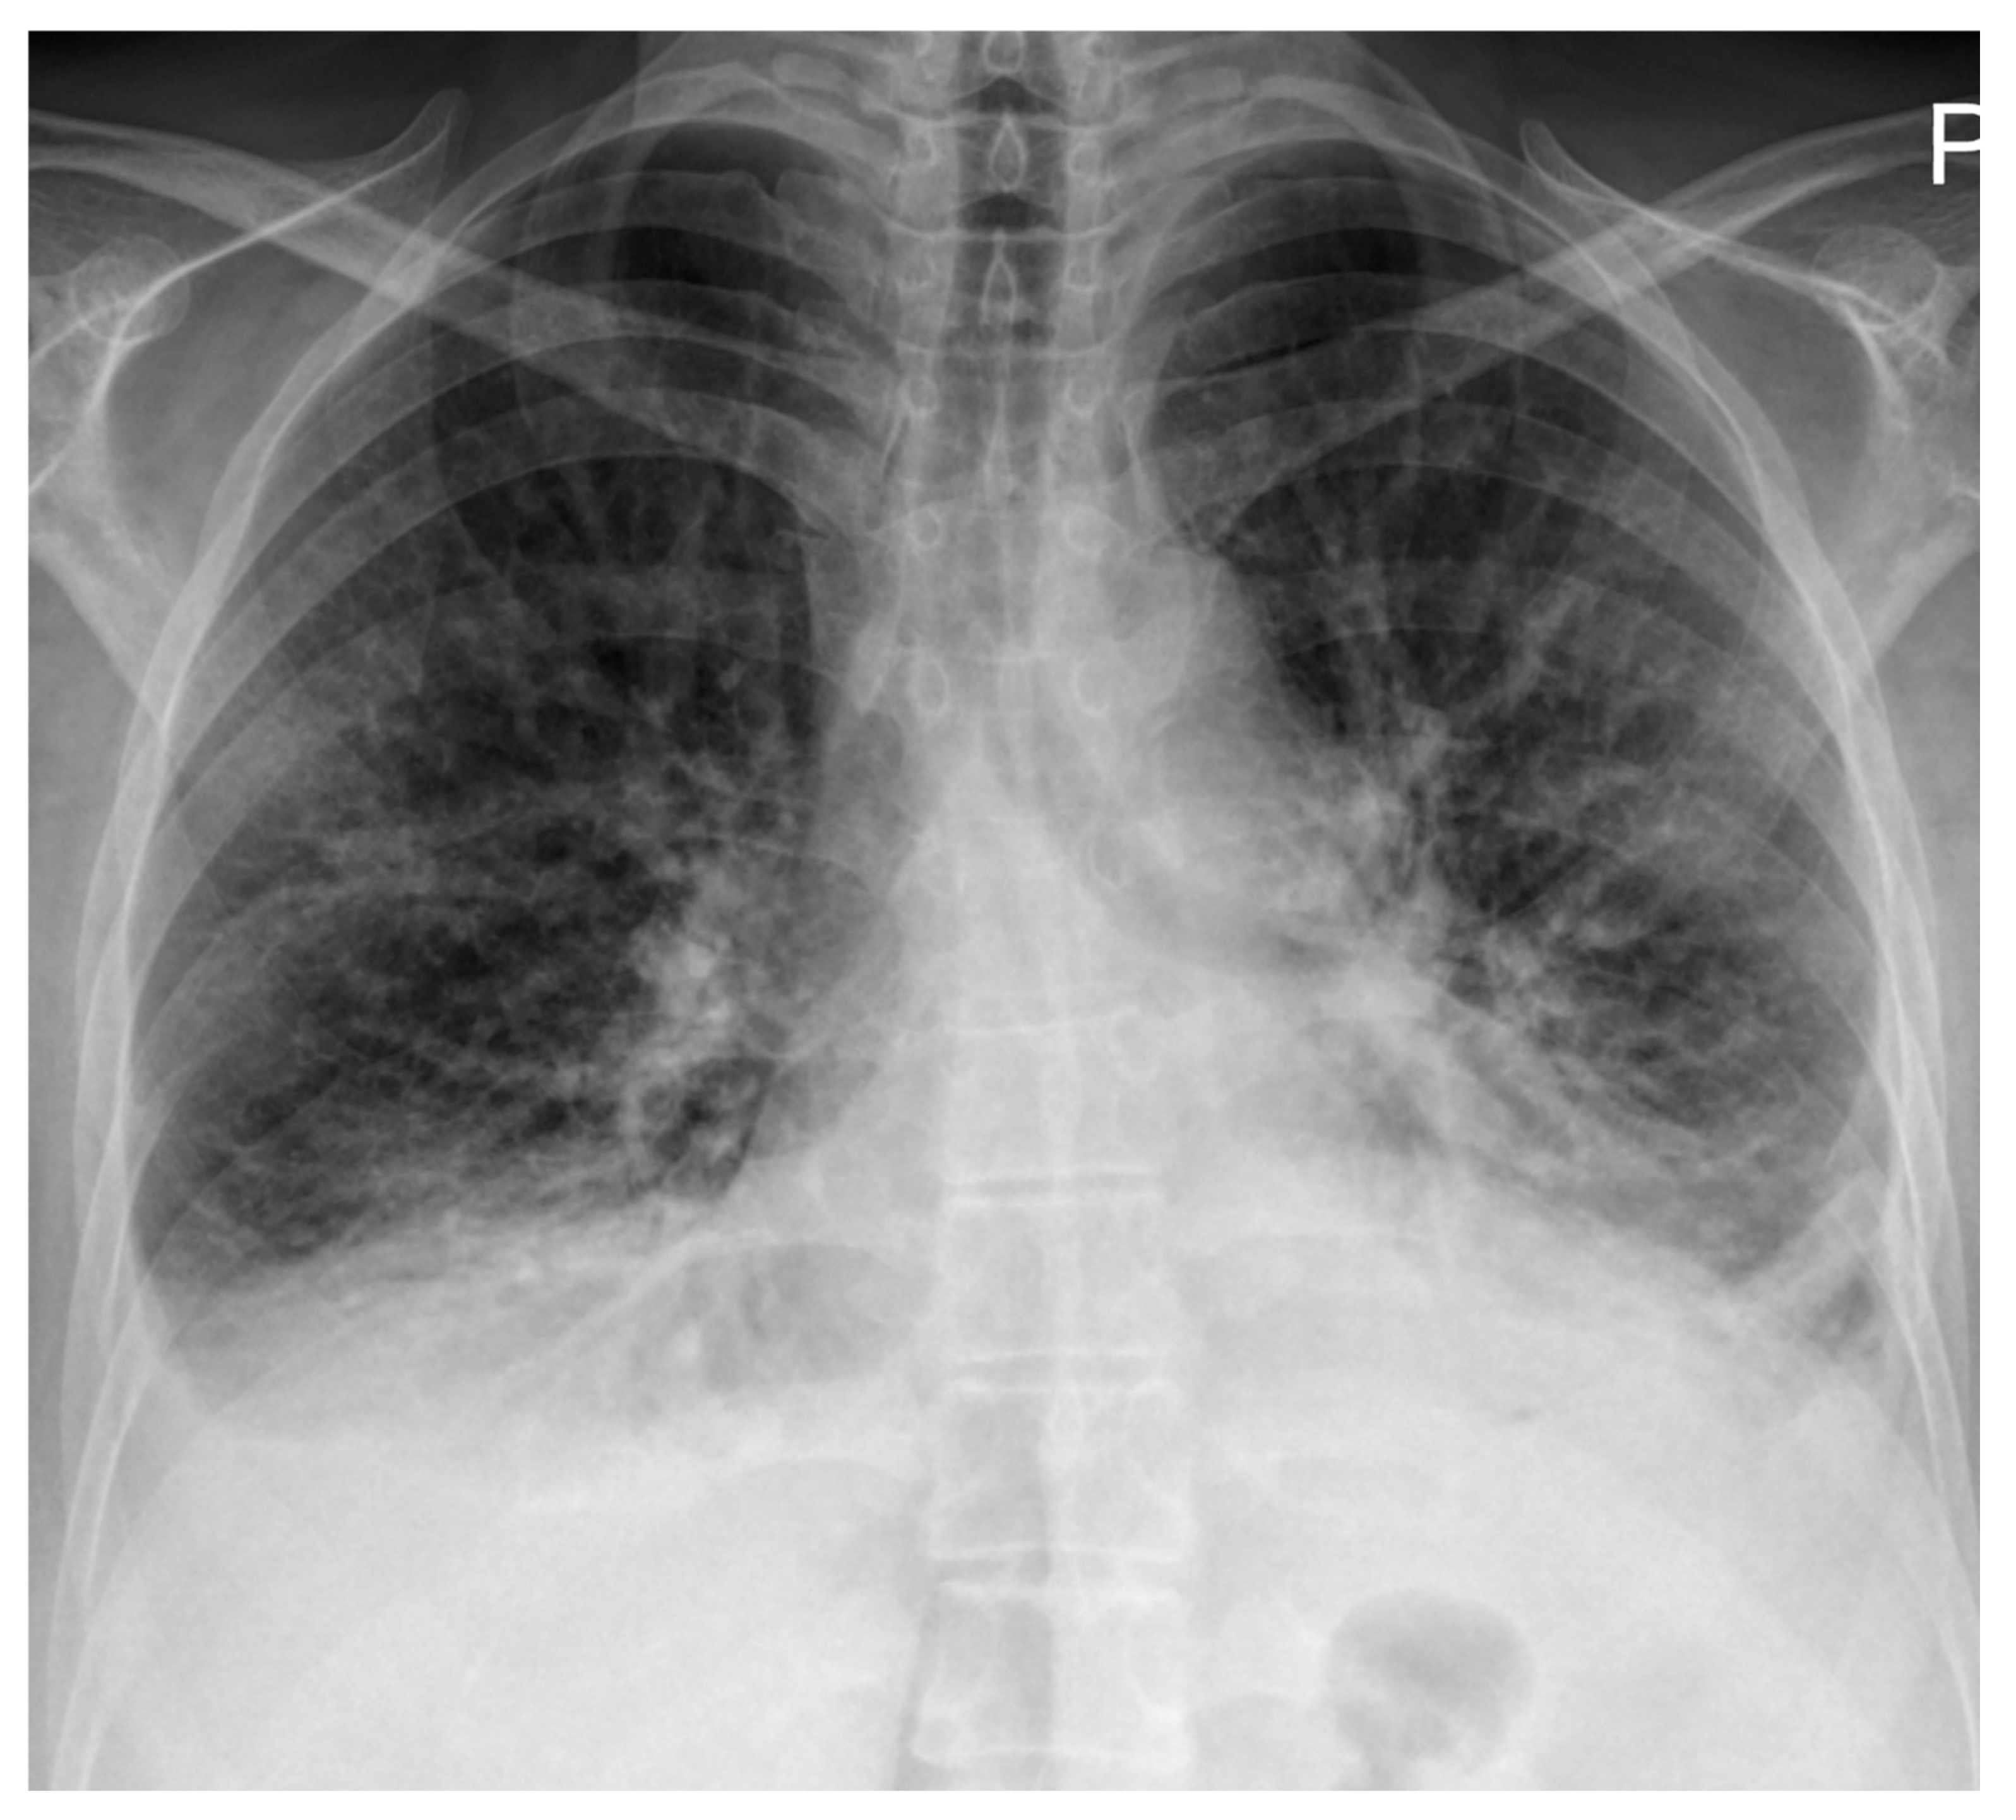

High-resolution computed tomography (HRCT) (Figure 2) showed markedly dilated pulmonary arteries, a small pericardial effusion, and absence of interstitial lung disease or features of pulmonary veno-occlusive disease. The “egg-and-banana sign” was observed (Figure 2D), with the main pulmonary artery appearing enlarged and ovoid (‘egg’) above the aortic arch (‘banana’), a pattern typically seen in pulmonary hypertension.

Figure 2. High-resolution computed tomography. (A) Normal lung parenchyma. (B) Small pericardial effusion (orange arrow). (C) Dilated main pulmonary artery measuring 30.7 mm (normal <27 mm in females). (D) The “egg-and-banana sign” in pulmonary hypertension: the dilated pulmonary artery (blue arrow, ‘egg’) seen above the lower margin of the aortic arch (green arrow, ‘banana’).